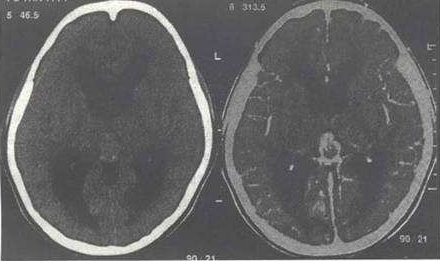

3、基底节生殖细胞瘤:多为男孩,早期出现肢体力弱或偏瘫,病程缓慢,影像特点为呈弥漫性生长,边缘欠清晰,形态不整,密度均匀,囊变、坏死和出血较常见。如肿瘤体大,但占位效应不明显、瘤旁水肿较轻,多伴有同侧外侧裂区大脑皮质萎缩。增强扫描时表现为不规则花环样强化或斑点祥强化。